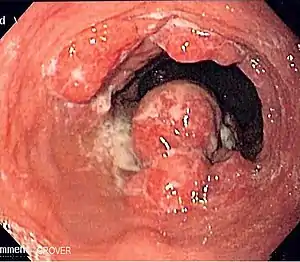

![]() Ендоскопічна картина раку стравоходу Ендоскопічна картина раку стравоходу | |